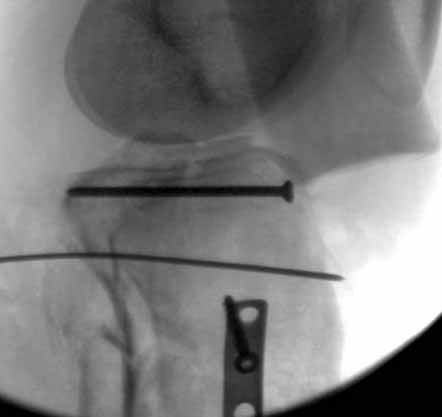

Двухколоннный перелом тибиал плато с вовлечением проксимального диафиза. Внутрисуставной компонент без смещения, и такой перелом можно лечить любым из описанных методов, о которых говорят наши коллеги.

Удобно аппаратом Илизарова или интрамедуллярным гвоздем. Гвозди не так сложно, как пугают, тем более Александр готов помощь с методичкой. Сперва надо установить компрессирующие шурупы на мыщелки. Давно отказались в пользу 3.5-4.0 мм кортикальных вместо толстых спонгиозных, потому что не доказаны преимущества толстых шурупов. Тонкие шурупы в субхондральной зоне смотрятся намного элегантнее, чем толстые 6.5.

Это мероприятие превращает перелом в простой диафизарный, который легко можно фиксировать гвоздем. Шурупы надо установить сзади предполагаемого места введения гвоздя.

В приложении этапы фиксации Both Column Fx и пластиной Synthes для плеча при переломе медиального мыщелка.